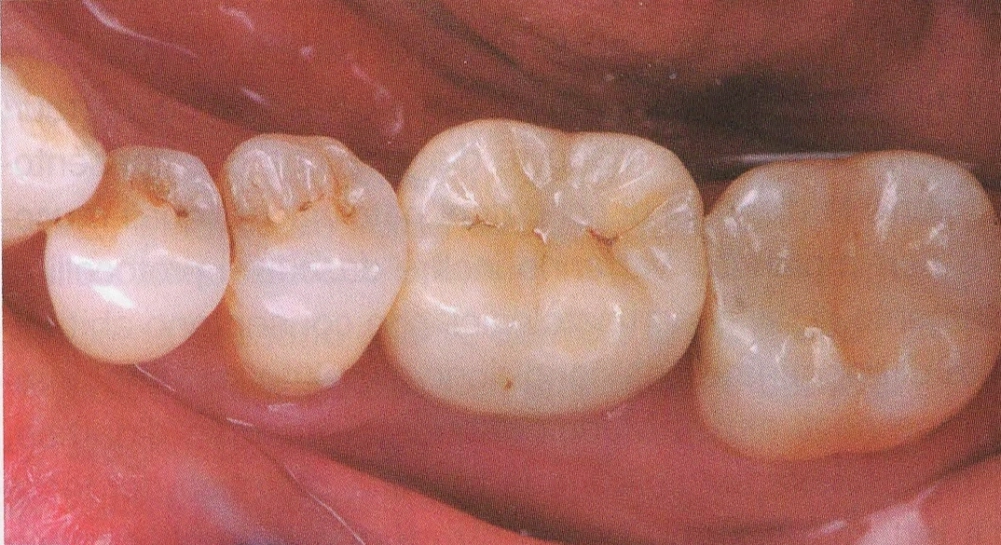

In questo studio vengono eseguite ceramiche di ultima generazione quali la zirconia ceramizzata, le ceramiche estetiche in disilicato senza trascurare le tradizionali metalceramiche. Il disilicato è un materiale altamente estestico che conferisce alla corona protesica un aspetto naturale e con questo materiale si possono creare manufatti con uno spessore molto ridotto.